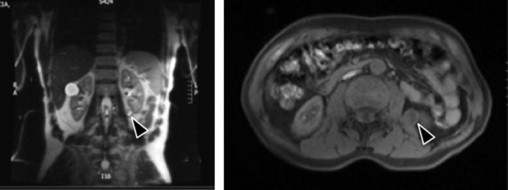

Homem de 61 anos com antecedentes de urolitíase. Fez uma ecografia de rotina onde se identificou uma imagem de natureza sólida pararrenal esquerda com cerca de 2 cm. Doente assintomático, sem dor abdominal ou no flanco. Dois meses depois efetua uma tomografia computadorizada e uma ressonância magnética que confirmaram uma lesão nodular pararrenal com 3 cm de maior diâmetro, de contornos bem definidos, com reforço heterogéneo em fase arterial, na face póstero‐inferior do rim esquerdo, junto ao músculo psoas maior (fig. 1 ). Perante a suspeita de tumor retroperitoneal primário de etiologia desconhecida e em crescimento progressivo realizou‐se uma laparoscopia exploradora.

Estudo imagiológico com corte coronal em T2 (esquerda) e corte axial à esquerda ...

Estudo imagiológico com corte coronal em T2 (esquerda) e corte axial à esquerda em T1 (direita).